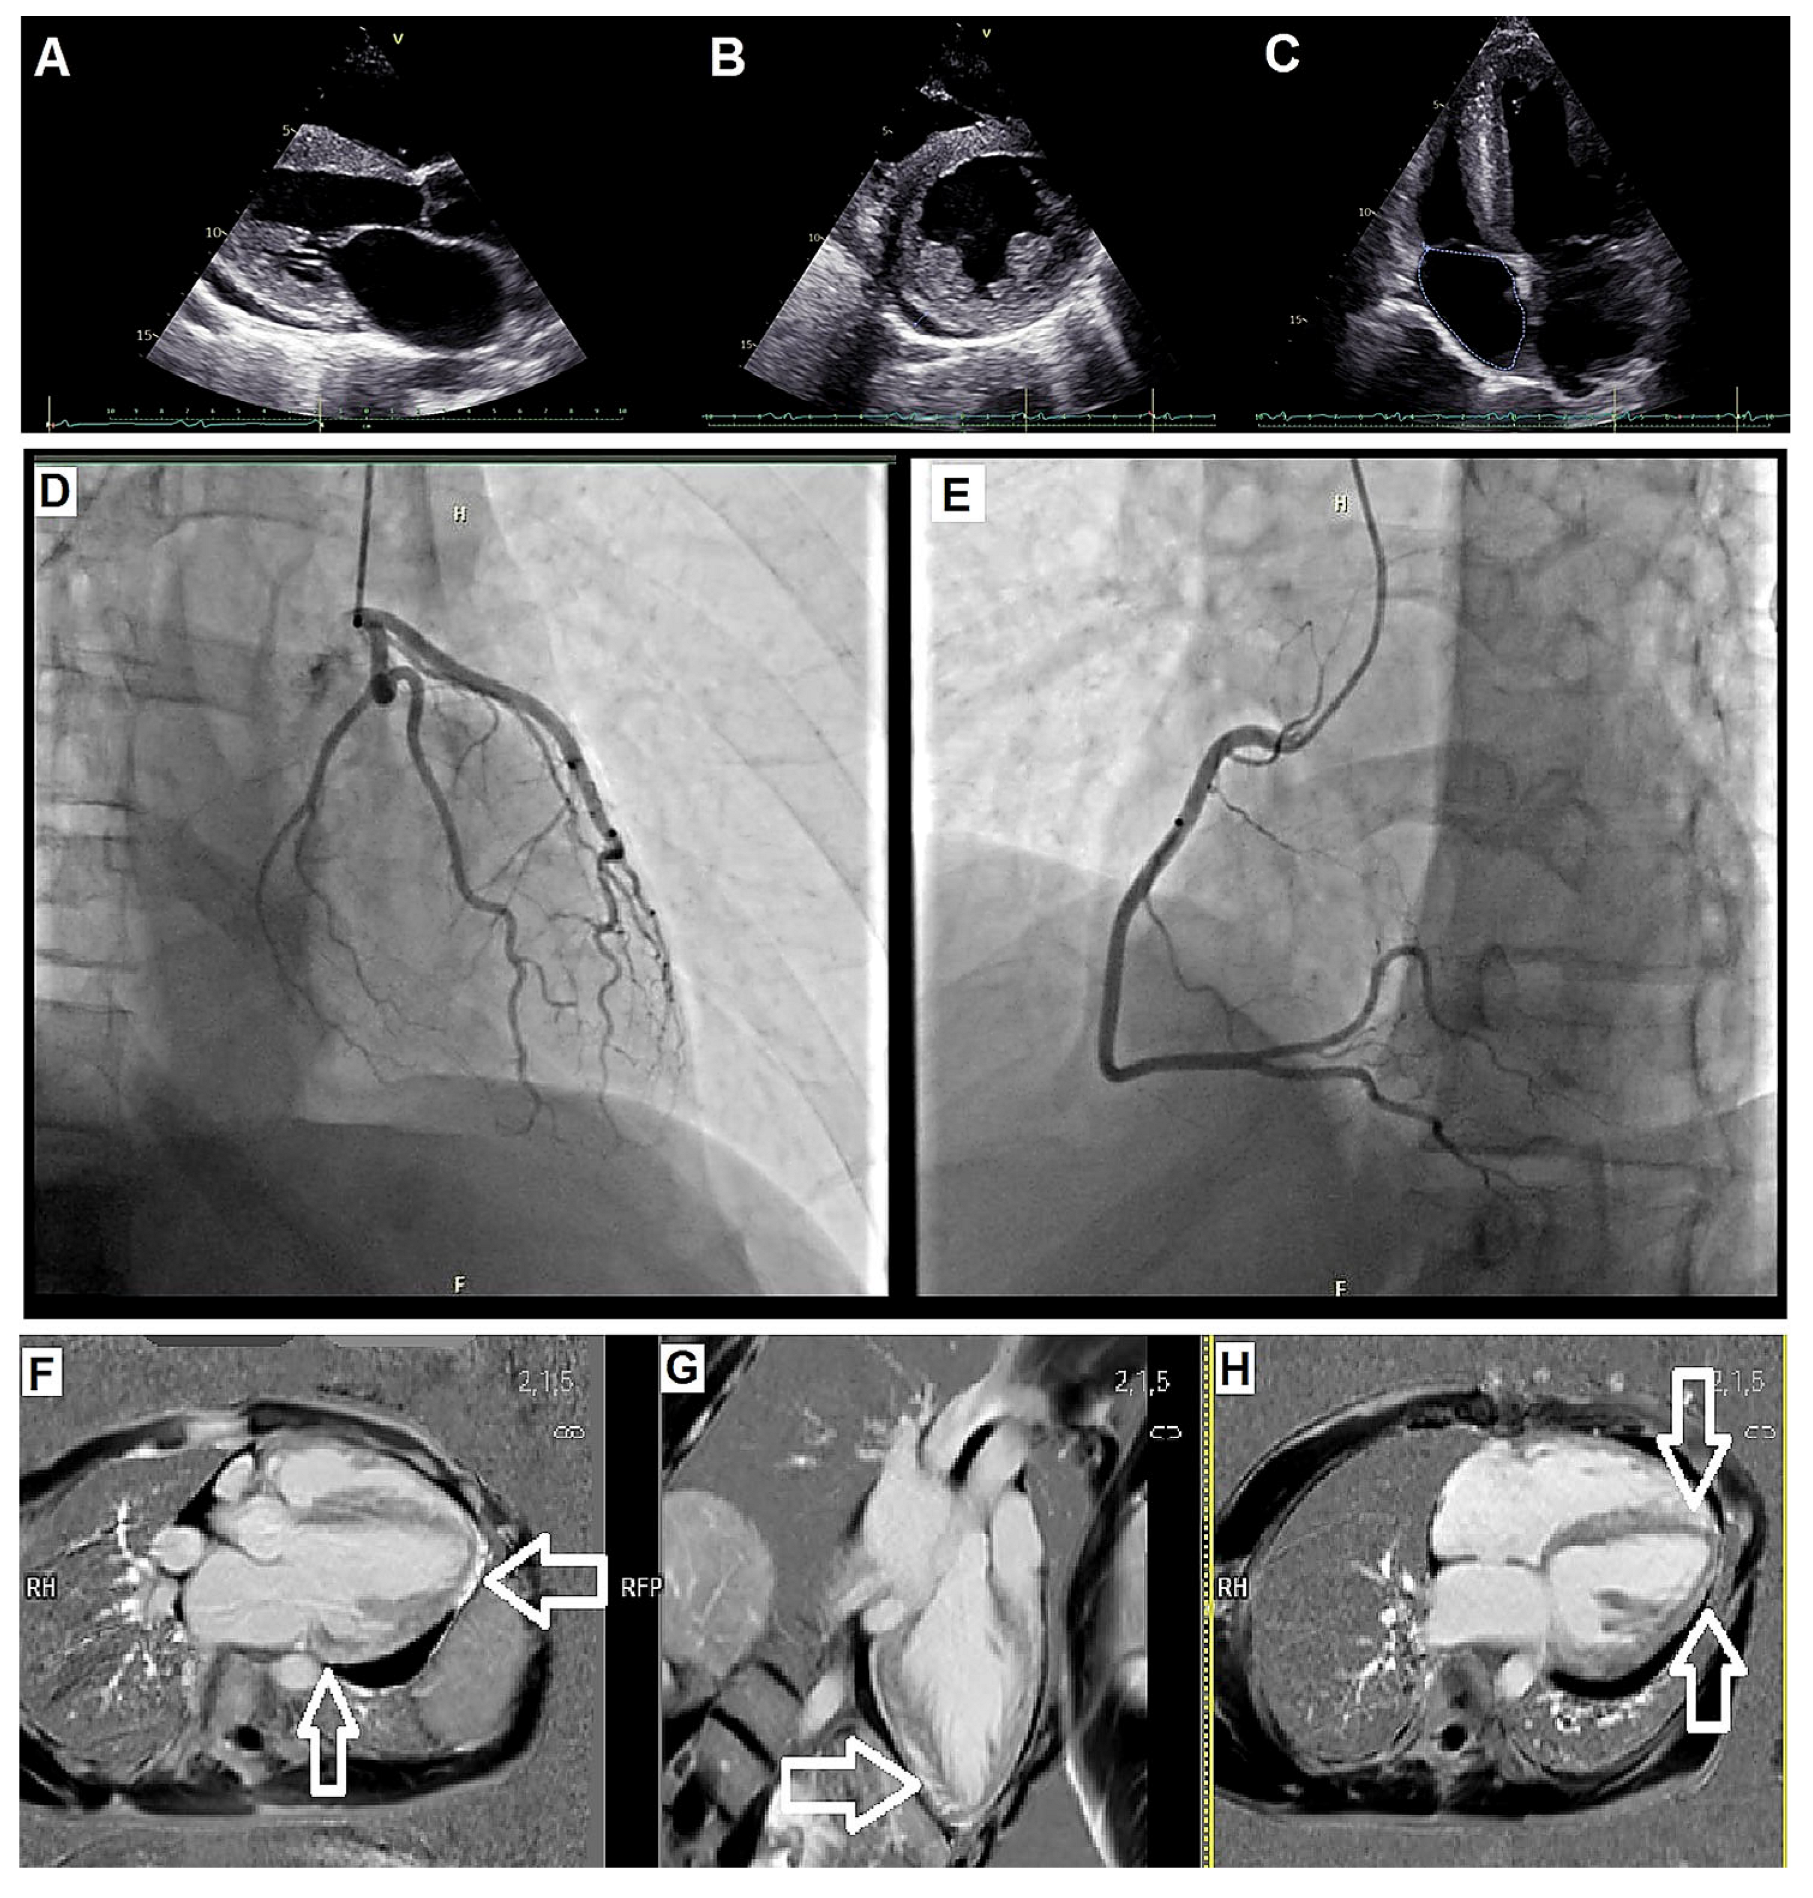

| Early hospitalization | LV hypertrophy + systolic dysfunction; pericardial effusion | TTE (details), CMR | Guideline-directed HF therapy as tolerated |

| Etiologic work-up | Exclusion of CAD; suspicion of systemic disorder | Coronary angiography; Fabry testing (α-galactosidase A); EMB | - |

| Additional diagnostics | Nondiagnostic EMB (performed at a tertiary center) | EMB | - |

| SCD prevention | Advanced HF with narrow QRS | Device selection | Single-chamber ICD implanted |

| Advanced HF pathway | Persistent severe LV dysfunction | Multidisciplinary evaluation | Evaluated for HTx |